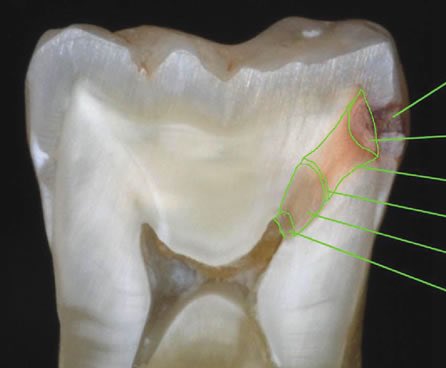

يحدث التسوس بين الأسنان بسبب تراكم بقايا الأكل في الفراغات الموجودة بين الأسنان ، وصعوبة وصول فرشة الأسنان للمكان، وفي الغالب يكون غير مرئي يعني سطح السن العلوي يكون سليم لكن التسوس من جانب السن.